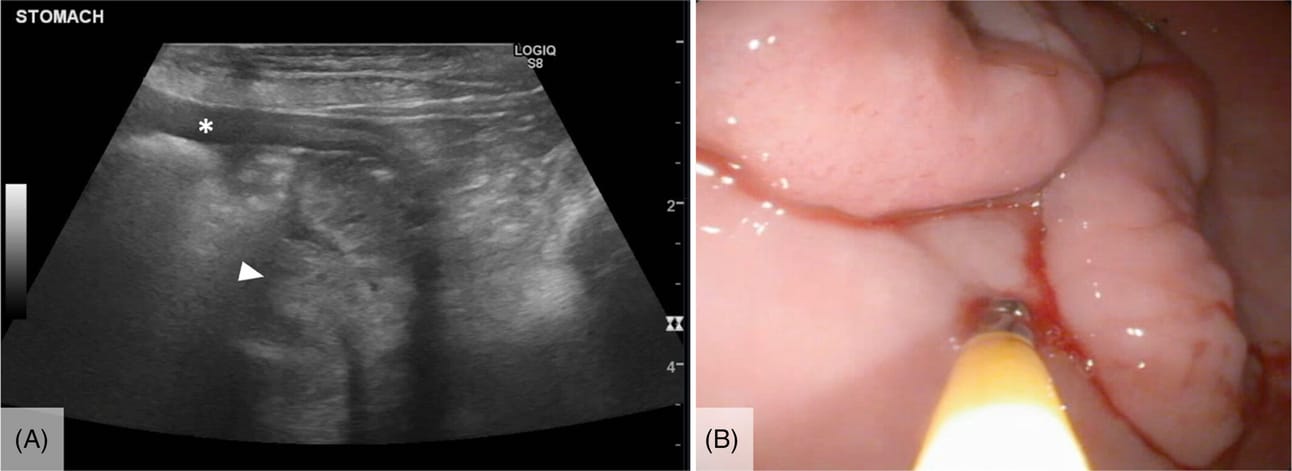

Abdominal ultrasound (A) and endoscopic (B) images of a serpentine gastric mass that was subsequently removed via gastrectomy and determined to be a gastric polyp on excisional biopsy. The gastric wall (asterisk) and gastric mass (arrowhead) on the ultrasonographic image (A) are identified.